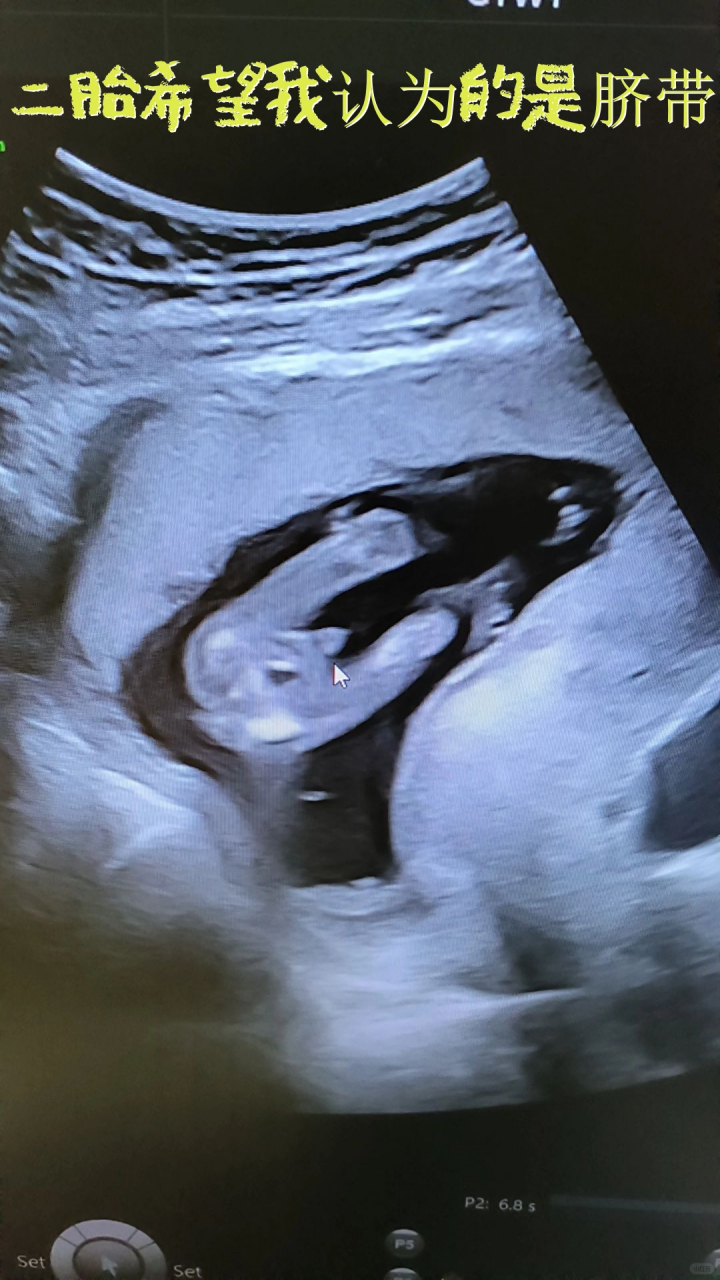

二胎希望我认为的是脐带 16周专门去看的,一胎知道是个儿子略失望,想

16周的b超图

16周的b超